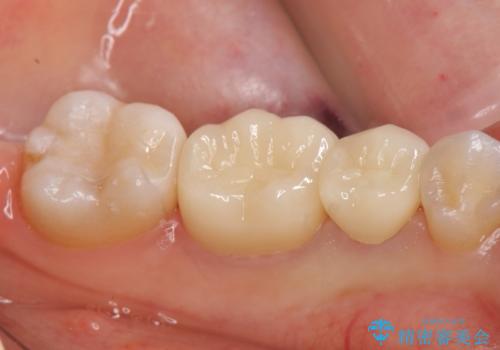

- 当院で前歯を治療中の患者様でしたが、左下1番奥の金属のつめものが外れたため、奥歯の治療もご希望されました。

その歯のすぐ後ろには埋まっている親知らずがあり、歯周ポケットも8mmありました(正常値3mm以下)。

このままでは適合のよい被せものを製作するのは難しいため、親知らず抜歯を行い、歯肉の位置が変化するのを待ってから被せものを製作しました。

外れたつめものの境目は歯肉の下でしたが、親知らずの抜歯を行うことで、歯肉の位置が変化して、境目が見えるようになり、適合のよい被せものを製作することができました。

今回のようなケースは、親知らず抜歯が有意義になります。